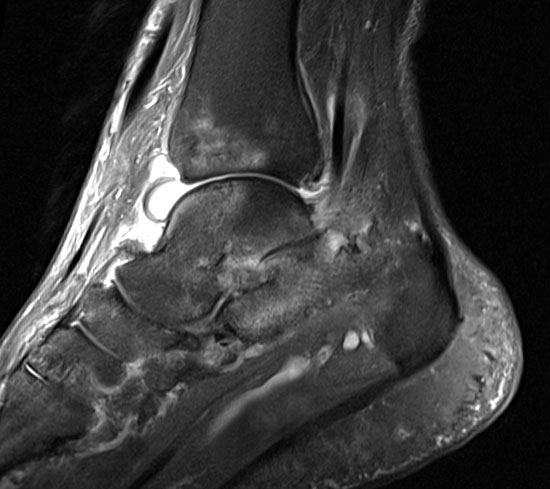

Szintigraphie, Computertomographie oder Kernspintomographie bleiben speziellen Fragestellungen vorbehalten wie z.B. Zystenausdehnung, Spontanfrakturen oder Osteonekrosen, die sich initial in der konventionellen Röntgenaufnahme nicht ausreichend darstellen. Die Szintigraphie hat außerdem ihren Stellenwert in der Frühdiagnostik, bei der Erfassung des Befallsmusters sowie beim Verdacht auf eine Endoprothesenlockerung.

In der Frühphase einer Rheumaerkrankung können mit der MRT bereits Veränderungen an den Gelenken und Weichteilen identifiziert werden, die im konventionellen Röntgen nicht sichtbar sind.

Abbildung 5